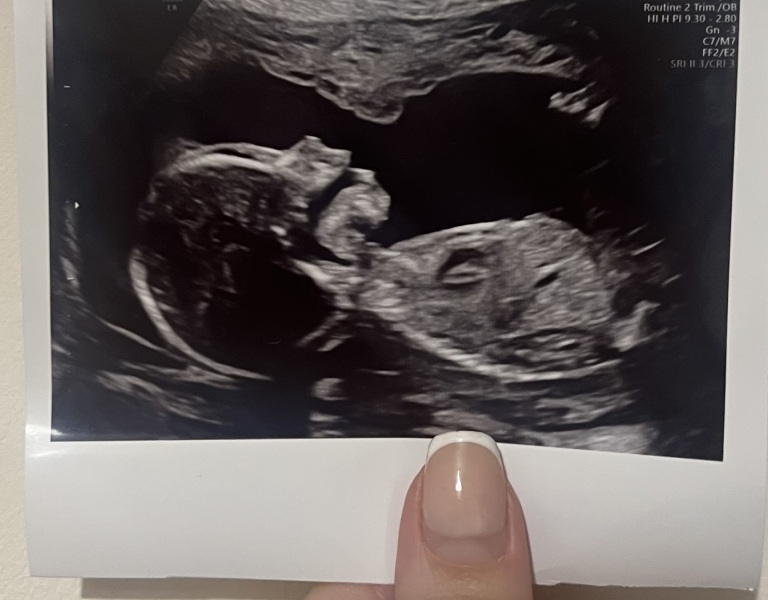

JDecember21 · 03/03/2025 11:30

@Brownbottle @sellingupslow hi ladies! Just wanted to say if you have your 20 week scan coming up hope it all goes well. I have mine later this afternoon and I’ll let you guys know how it goes. Hope you’re all doing well. I’ve started to feel movements last few weeks!! Xx

so pleased as today the 20 week scan went perfectly literally everything is ‘normal’ they said. So that was a huge relief.